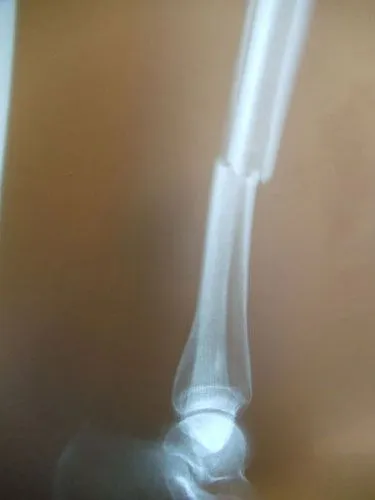

Pictures below show a 60 year old woman who fell getting out of bed and broke the shaft of her tibia as has a distal fibular fracture. This was treated with an Intramedullary rod as well as a surgical plate and fixation with screws of the fibular fracture.

Displaced Tib-fib fracture that was treated with IM rod of the Tibia (below)